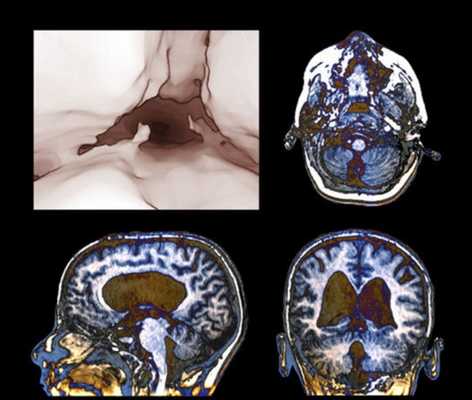

Внутренняя тривентрикулярная окклюзионная гидроцефалия на МРТ во фронтальной и сагиттальной плоскостях: на левом снимке видно гигантское кистозно-солидное образование, явившееся причиной обструкции ликворопроводящих путей на уровне Сильвиева водопровода